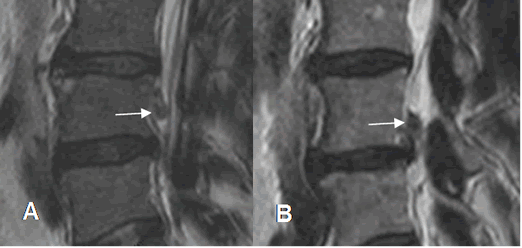

Fig 108. Regresión de hernia.

A y B: RM sagital en GE. Hernia paramediana derecha. En un control 2 años después, ha disminuido la compresión del saco dural.

Fig 109. Regresión de hernia.

A y B: RM axial en T2. Hernia paramediana derecha. En un control posterior, ha disminuido el tamaño y la compresión de las raíces.

Fig 110. Regresión de hernia.

A y B: RM sagital en T2. Hernia mediana en L3-L4, que después de 7 meses, muestra disminución de su tamaño y menor compresión del saco dural. Cambios degenerativos en las placas terminales de L3-L4 y

L4-L5 y artefactos sobre el cuerpo de L4, ocasionados por materia de fijación posterior. (Puntas de flecha).